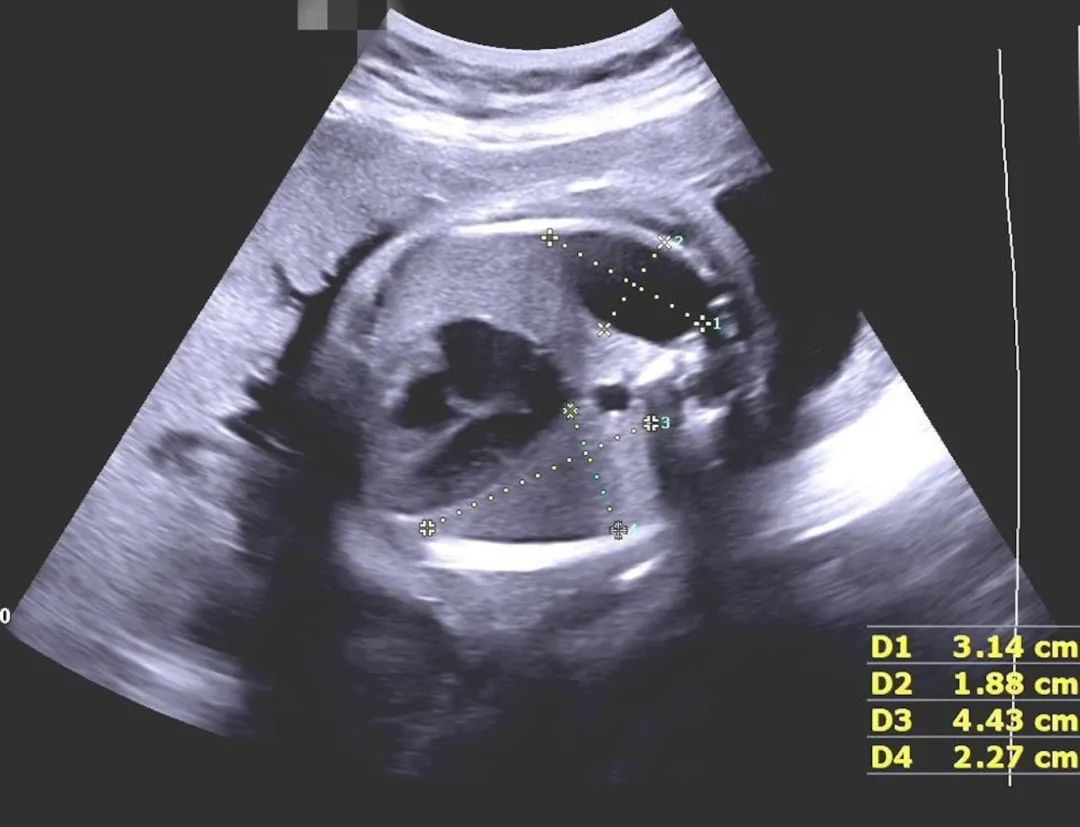

緊急會診

接診后,許茜主任聯(lián)合胎兒醫(yī)學團隊和心胸外科團隊,快速對粒粒的情況進行了評估:單絨毛膜雙胎,雙胎之一發(fā)育落后,臍血流異常,伴有多發(fā)畸形,預后不良,隨時可能胎心消失;雙胎之二左側(cè)膈疝,膈疝預后主要取決于肺發(fā)育的情況,經(jīng)過專業(yè)評估,孩子肺發(fā)育各項指標良好,評估LHR 2.6,觀測/期待LHR50%,出生后手術(shù)干預效果好,存活率接近100%。